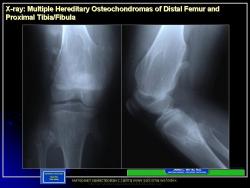

Иллюстрации из литературных источников.

Приложения:

14.N.Slayd15.JPG15.N.Slayd16.JPG16.N.Slayd17.JPG17.N.Slayd18.JPG18.N.Slayd19.JPG19.N.Slayd20.JPG1.1.Slayd20.JPG2.2.Slayd21.JPG3.3.Slayd22.JPG210.OH_.Slayd25.JPG